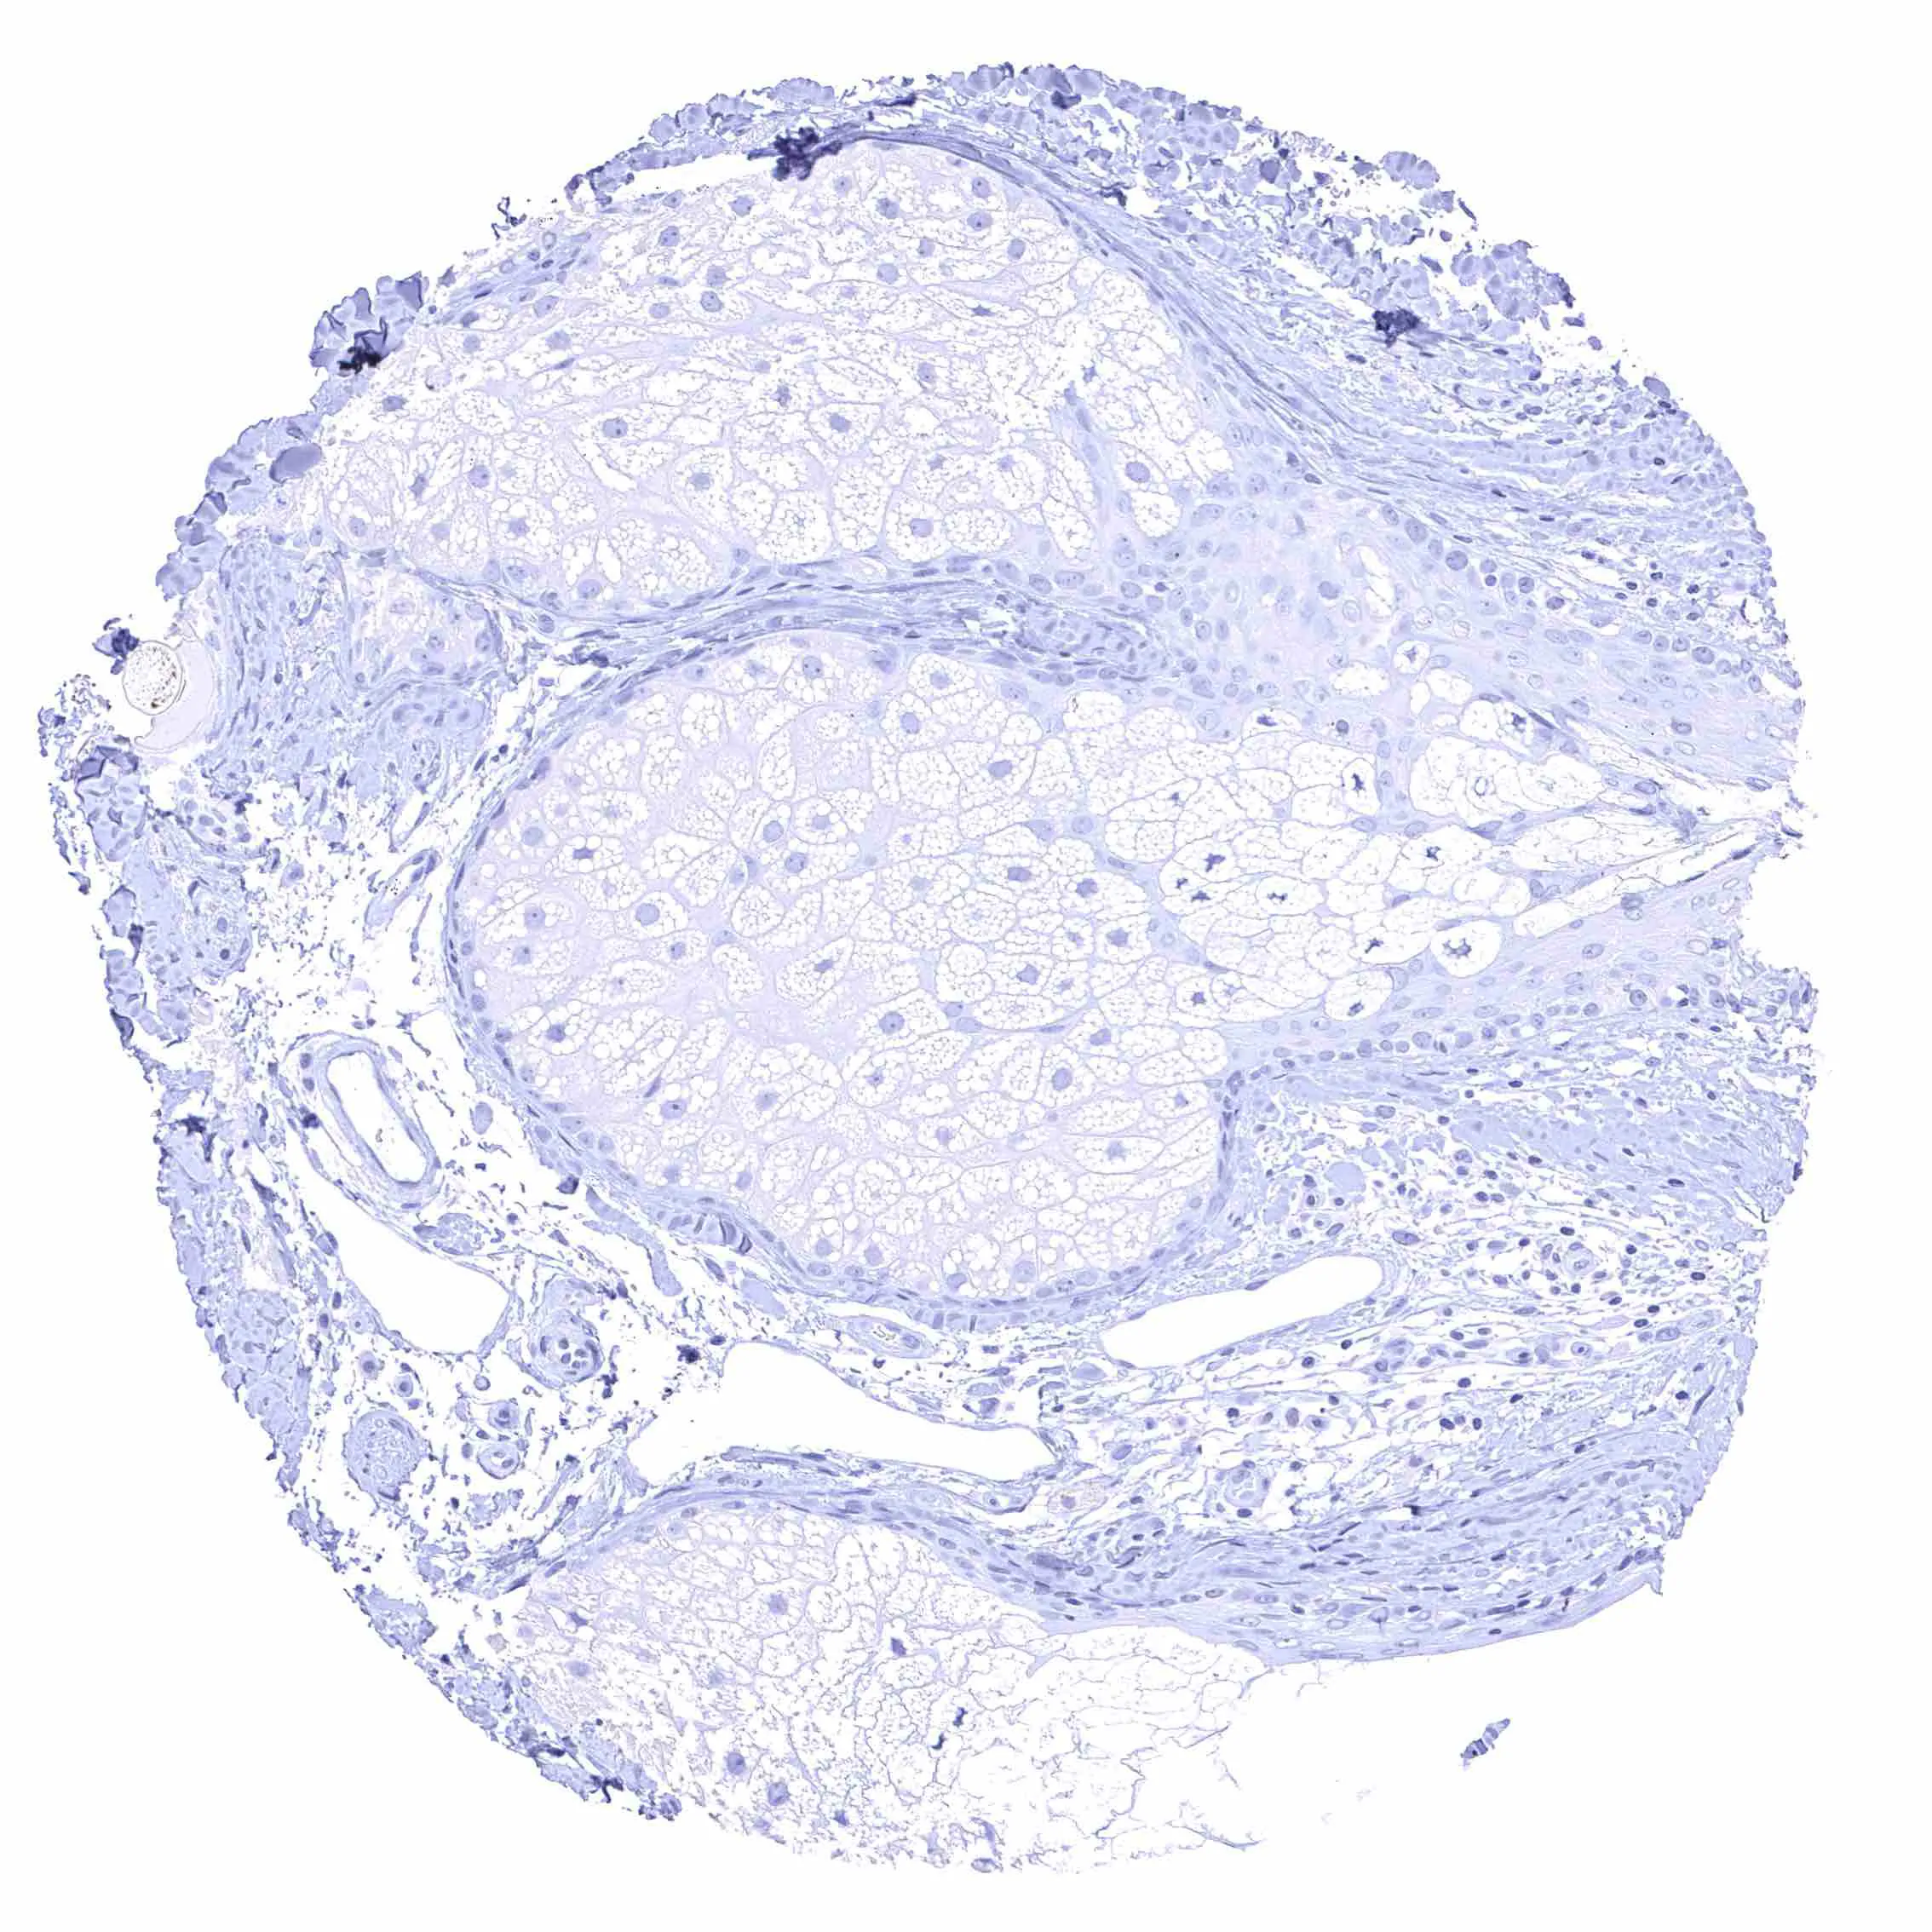

Liver